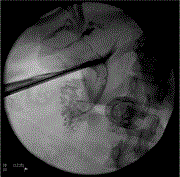

A case of anterior choroidal artery occlusion test under MEP monitoring for a recurrent internal carotid artery–anterior choroidal artery bifurcation aneurysm clipping

Yosuke Suzuki and others

Journal of Surgical Case Reports, Volume 2023, Issue 1, January 2023, rjac639, https://doi.org/10.1093/jscr/rjac639